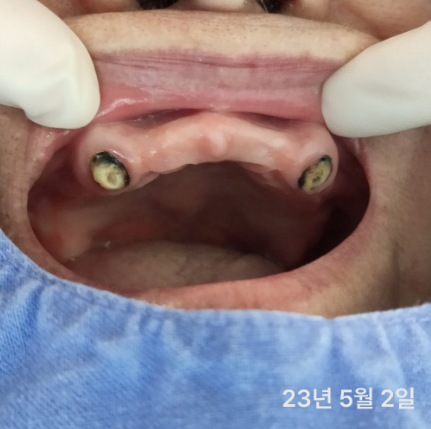

실제 환자분들의 깨끗한 통지르코니아 잇몸 반응